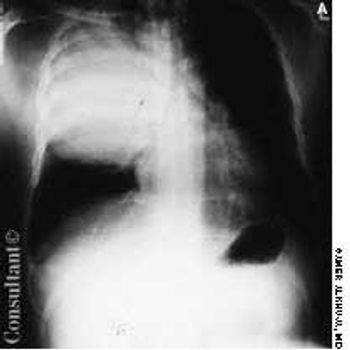

A 70-year-old man with a history of peptic ulcer disease presented with a 1-dayhistory of epigastric pain. Abdominal examination revealed mild epigastrictenderness. A pneumoperitoneum was discovered on a chest film (A), and aleft decubitus chest film (B) confirmed this diagnosis.